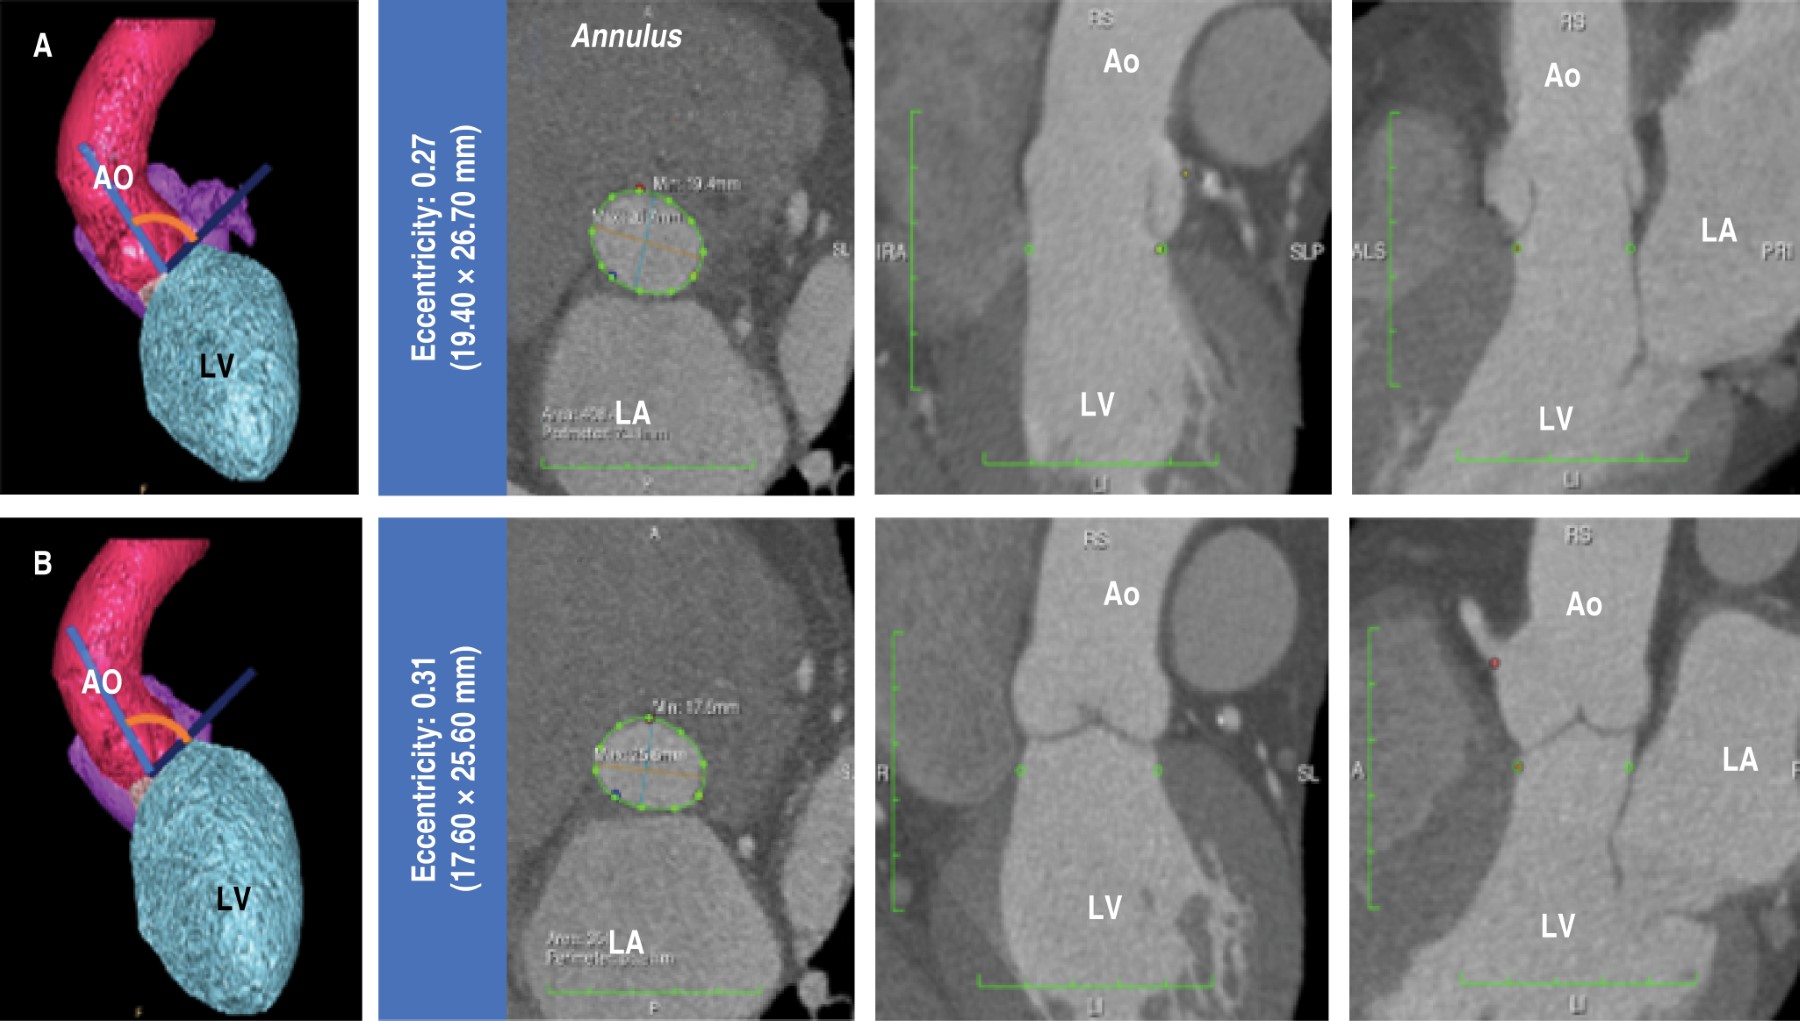

Introducción: Los rasgos específicos de la raíz aórtica parecen tener algunas implicaciones clínicas y pronósticas, y las diferencias relacionadas con el sexo se han descrito previamente. Sin embargo, faltan datos sobre la población mexicana. Objetivos: Describir las discrepancias relacionadas con el sexo con respecto a las características de la raíz aórtica en un análisis estructural y funcional. Material y métodos: Se analizaron los datos de hallazgos de la tomografía computarizada cardiaca de la raíz aórtica en 71 pacientes mexicanos con válvula aórtica de trivalva, sin estenosis valvular ni antecedentes de aneurisma de la aorta. Se dividió la población para describir las desviaciones específicas por sexo; mujeres 53.5% (n = 38) y hombres 46.5% (n = 33). La mediana de edad fue de 56 años (IQR: 49-64) con una prevalencia similar de hipertensión, diabetes, tabaquismo y dislipidemia. El peso, altura y área de superficie corporal (ASC) fueron significativamente más bajos en las féminas, sin divergencias en el índice de masa corporal. No hubo disparidades notorias con respecto a la excentricidad del anillo aórtico durante la sístole y la diástole y la angulación de la aorta durante la diástole. No obstante, la angulación aórtica durante la sístole fue mayor en mujeres y las dimensiones del anillo aórtico en sístole resultaron ostensiblemente más altas en varones. Las magnitudes de la raíz aórtica se revelaron superiores en los hombres, pero cuando se indexaron a ASC fueron más elevadas en las señoras. Se encontró un anillo aórtico pequeño en 71% de las féminas y 18.1% de los varones, y una raíz aórtica pequeña fue significativamente mayor en los señores en comparación con las señoras (30.3% versus 2.6%, p = 0.001). Conclusiones: Características individuales como el peso, estatura y ASC tienen consecuencias al comparar las dimensiones aórticas. Las diferencias de estos parámetros entre sexos, como la baja estatura corporal en las mujeres mexicanas, podrían explicar la alta prevalencia de un anillo aórtico pequeño, especialmente cuando la medida se indexa por altura del cuerpo y las otras particularidades de la aorta a diferentes niveles. Las implicaciones clínicas de estos hallazgos permanecen inciertas.

Figura 2